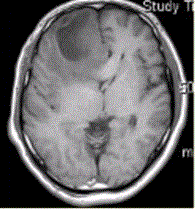

问题 患者女,67岁,头痛伴呕吐1周。既往体健。MR表现如下图。 胶质瘤术后放疗后复发与放射性坏死的鉴别手段是

选项 A.T2* B.PWI C.DWI D.Gd-MRI E.FLAIR

答案 B